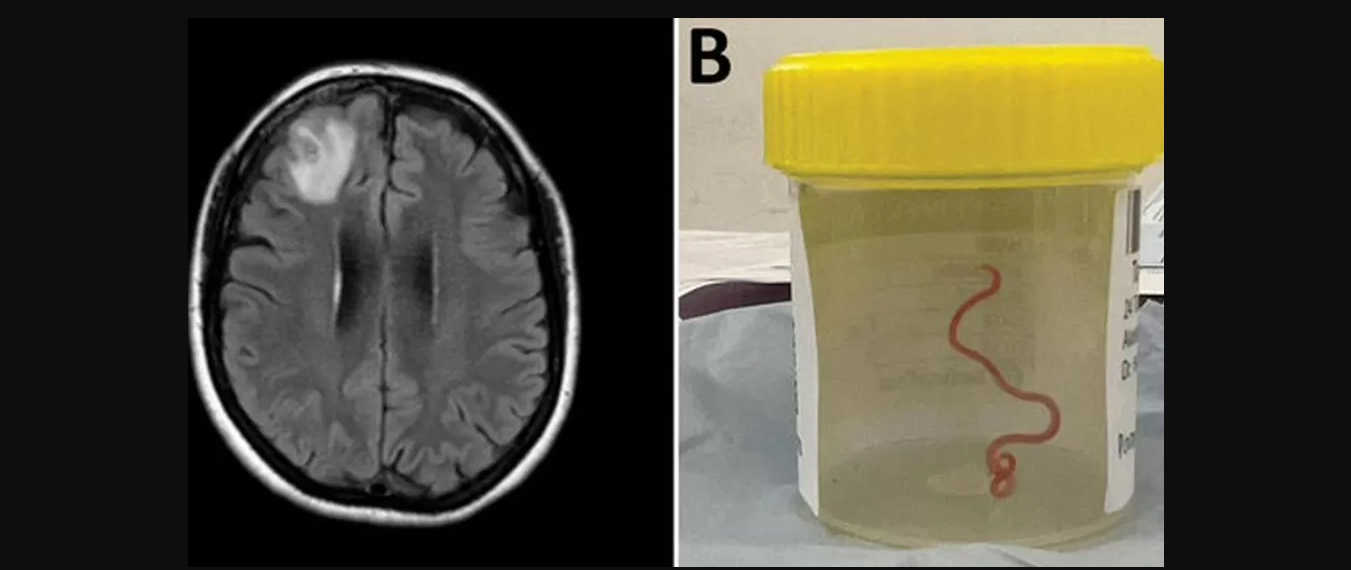

गत वर्ष क्यानबेरामा गरिएको शल्यक्रियामा बेलायतमा जन्मेका बिरामीको टाउकाको अगाडिको भाग (फ्रन्टल लोब)मा रहेको तन्तुबाट धागो (स्ट्रिङ) जस्तो किरा निकालिएको थियो ।

जनावरबाट मानिसमा सर्ने रोग र संक्रमणको बढ्दो खतरालाई यस तथ्यले उजार गरेको अनुसन्धानकर्ताले चेतावनी दिएका छन् । क्यानबेरा अस्पतालका सङ्क्रामक चिकित्सक सञ्जय सेनानायकेले भने, ‘शल्यक्रिया गर्ने थियेटरमा भएका सबै जना स्तब्ध भएका थिए, जब सर्जनले असामान्य चीज उठाउन फोर्सेप लगाए, त्यो असामान्य चीज ८ सेन्टिमिटरको हल्का रातो कीराको रुपमा निस्कियो ।’

बिरामीलाई सन् २०२१ को जनवरीको अन्त्यमा अस्पताल भर्ना गरिएको थियो । परीक्षण गरेर हेर्दा उनको मस्तिष्कको दाहिनेतिरको अगाडिको लोबभित्र असामान्य चोट देखिएको थियो । उनको अवस्थाका कारण सन् २०२२ को जुनमा गरिएको बायोप्सीको क्रममा यो विषय थाहा भएको थियो ।